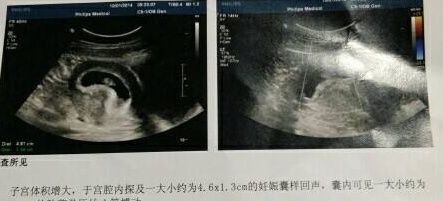

1,肾盂分离

相信我们的准妈妈,在做完B超之后,如果B超上出现肾盂分离这四个字的时候,我们的准妈妈可能就会感觉到非常的担心。好奇是不是自己腹中的宝宝出现了一系列的问题?那么真实情况下真的是这样吗?其实我们的孕妈不用太过担心,因为这都是在怀孕期间宝宝出现的一些正常的现象。有可能是宝宝憋尿憋的,然后才造成了肾盂分离的现象。等到宝宝出生之后,尿一泡尿,可能就没有其他问题了。因此我们的,孕妈不用太过担心,而且可以通过这项活动,可以推测出,一般男孩子才会发生肾盂分离,而这种现象出生在女孩子的身上的时候少之又少,因此如果出现的时候,很有可能是肚子里怀的是一个男宝宝。我们的孕妈应该提前高兴才是。